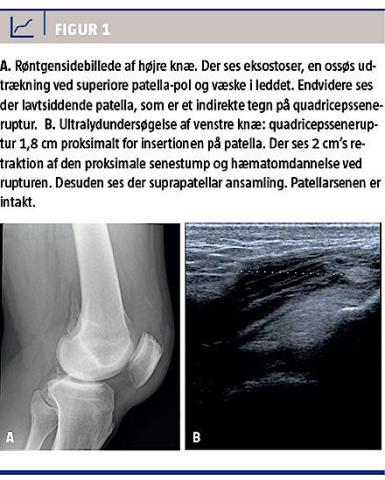

Patienten blev tilset på skadestuen, hvor brud i begge knæ blev udelukket ved en røntgenoptagelse (Figur 1A). Ved en objektiv undersøgelse fandt man ved Lachmans test løshed i venstre knæ samt fri aktiv fleksion og ekstension over begge knæled. Den initiale mistanke var en læsion af forreste korsbånd, som blev behandlet med knæskinne. I ambulatoriet to uger senere konstateredes bilateral palpabel defekt proksimalt for patella og total ekstensionsdefekt over knæleddene. Sekundært var der ingen mistanke om korsbåndslæsion. Diagnosen BQTR blev bekræftet ved ultralydskanning (Figur 1B).